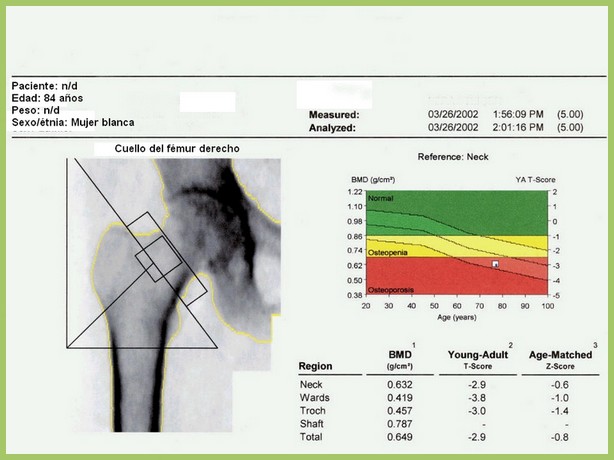

Eficacia de un programa poblacional de rastreo de osteoporosis en mujeres de 70 a 85 años

Se calculó el puntaje FRAX y se realizó densitometría a aquellas con riesgo de fractura elevado, dejando el tratamiento a criterio del médico de cabecera. Se logró una reducción del 28% (IC 11-41%) de las fracturas de cadera. The Lancet, 15 de diciembre de 2017

Densitometría ósea: poco cumplimiento de las recomendaciones

En este estudio argentino, la mitad de las densitometrías se pidieron en mujeres que no cumplían los criterios recomendados de edad o de riesgo aumentado para justificar el rastreo de osteoporosis. Salud Colectiva, octubre de 2016